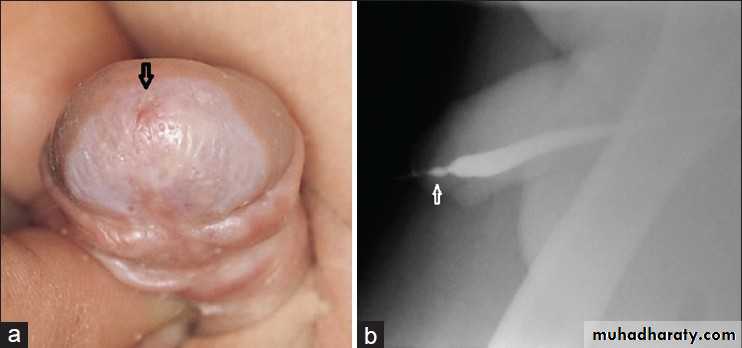

PHIMOSIS

BackgroundAt the end of the first year of life, retraction of the foreskin behind the glanular sulcus is possible in only about 50% of boys.

The phimosis is either primary (physiological), with no sign of scarring, or secondary (pathological), resulting from scarring due to conditions such as balanitis xerotica obliterans.

Phimosis must be distinguished from normal agglutination of the foreskin to the glans, which is a physiological phenomenon.

Paraphimosis

It is characterised by retracted foreskin with the constrictive ring localised at the level of the sulcus.A dorsal incision of the constrictive ring may be required, or circumcision is carried out immediately or in a second session.